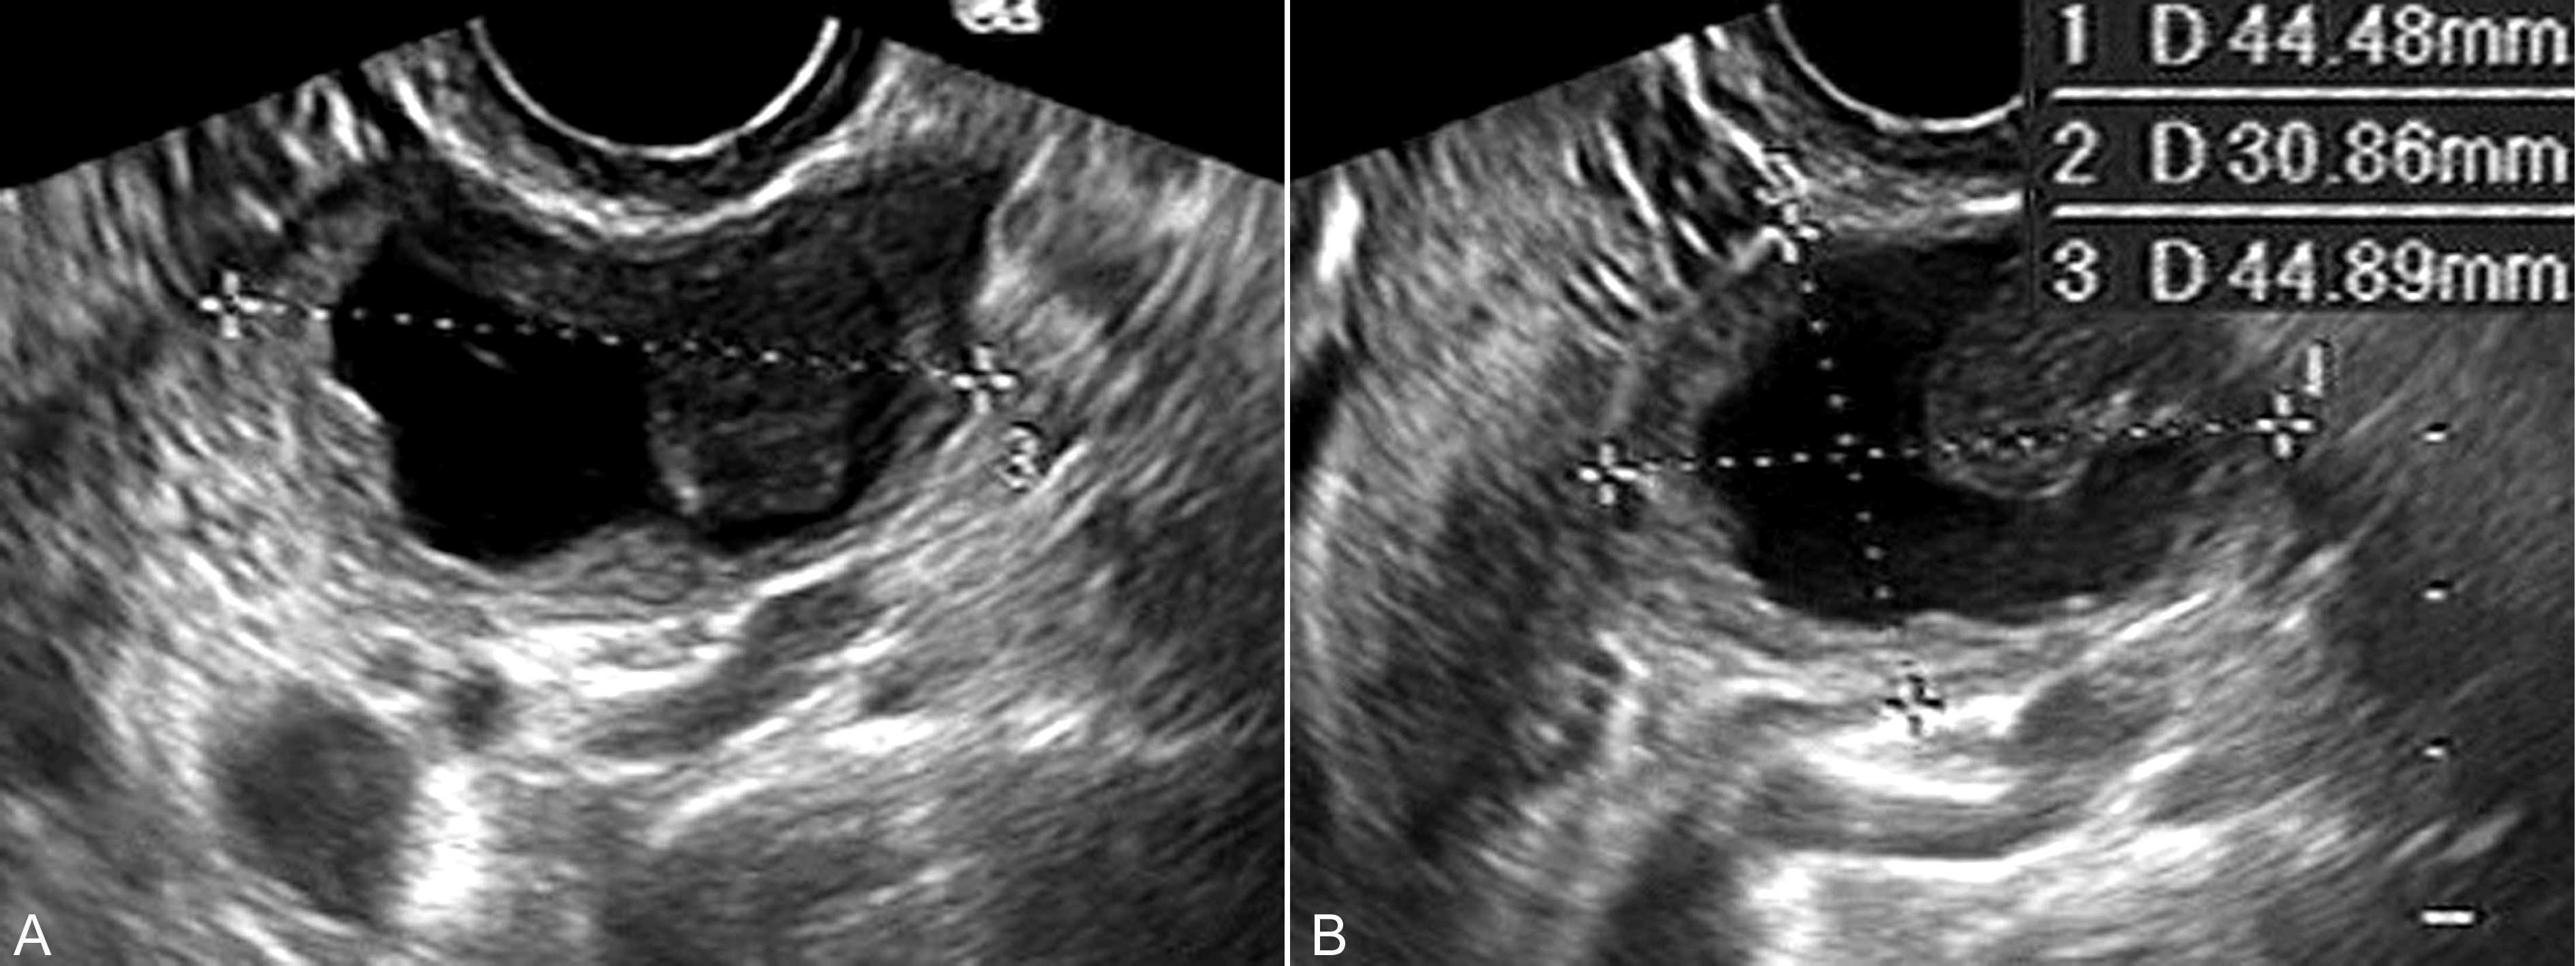

图6卵巢恶性粘液瘤声像图

C、D:瘤体内为无回声,一侧可见不规则乳头状回声,测量为20mm × 14mm × 15mm